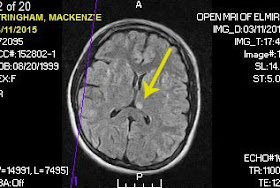

|

| The bike. |